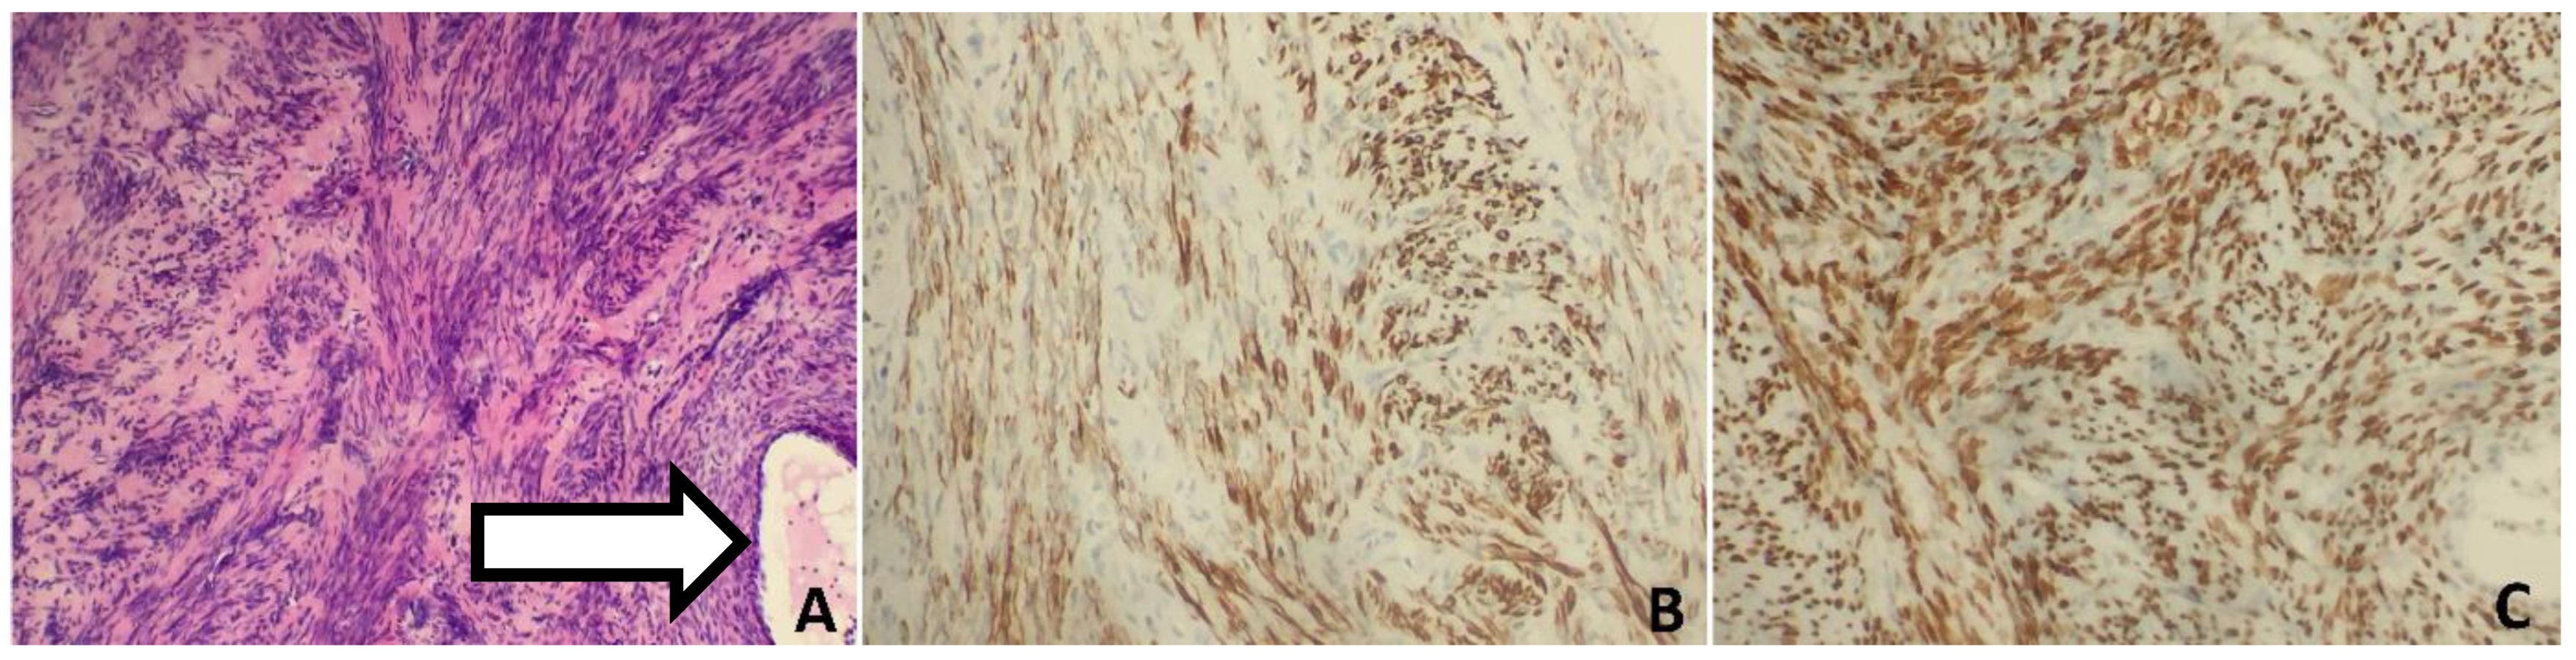

3. Case 2